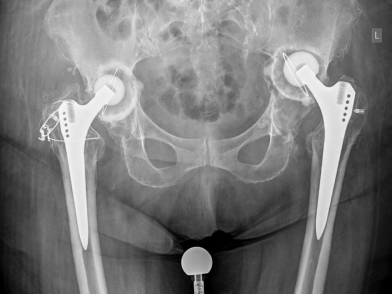

Η ολική αρθροπλαστική ισχίου (ΟΑΙ), είναι η αντικατάσταση της άρθρωσης του ισχίου και είναι μια εξαιρετικά επιτυχημένη χειρουργική επέμβαση που αποσκοπεί στην ανακούφιση του πόνου και στην αποκατάσταση της λειτουργικότητας σε ασθενείς που πάσχουν από σοβαρή αρθρίτιδα του ισχίου. H ολική αρθροπλαστική ισχίου δημιουργεί σημαντική βελτίωση της ποιότητας ζωής, ωστόσο ορισμένοι ασθενείς μπορεί να εμφανίσουν επιπλοκές. Μια σημαντική επιπλοκή είναι η χαλάρωση της πρόθεσης. Η κατανόηση των αιτίων, των συμπτωμάτων, της διάγνωσης και των επιλογών θεραπείας της χαλάρωσης των προθέσεων μπορεί να βοηθήσει τους ασθενείς να λάβουν ενημερωμένες αποφάσεις και να αναζητήσουν έγκαιρη ιατρική παρέμβαση.

Η ολική αρθροπλαστική ισχίου περιλαμβάνει τη χειρουργική αντικατάσταση του κατεστραμμένου χόνδρου και οστού στην άρθρωση του ισχίου με προθέσεις κατασκευασμένες από τιτάνιο, πολυεθυλενιο ή κεραμικά υλικά. Αυτές οι προθεσεις έχουν σχεδιαστεί για να μιμούνται τη φυσική κίνηση του ισχίου, παρέχοντας με αυτό τον τρόπο ανακούφιση από τον πόνο και βελτιωμένη κινητικότητα. Συνήθως, συνιστάται για ασθενείς με σοβαρή οστεοαρθρίτιδα ή ρευματοειδή αρθρίτιδα, οι οποίοι δεν έχουν βρει ανακούφιση από συντηρητικές θεραπείες όπως είναι τα φάρμακα, η φυσιοθεραπεία ή οι ενέσεις.

Η περιπροθετική χαλάρωση είναι μία από τις πιο συχνές μακροπρόθεσμες επιπλοκές μετά την ολική αρθροπλαστική ισχίου. Συμβαίνει όταν η οστεοενσωμάτωση μεταξύ πρόθεσης και οστού αποτυγχάνει, προκαλώντας σαν αποτέλεσμα αστάθεια του εμφυτεύματος. Διάφοροι παράγοντες μπορούν να συμβάλουν στη χαλάρωση:

Η διάγνωση της περιπροθετικής χαλαρωσης περιλαμβάνει συνδυασμό κλινικού, απεικονιστικού και μερικές φορές εργαστηριακού ελεγχου. Οι απεικονιστικές μελέτες που χρησιμοποιούνται συνήθως είναι: